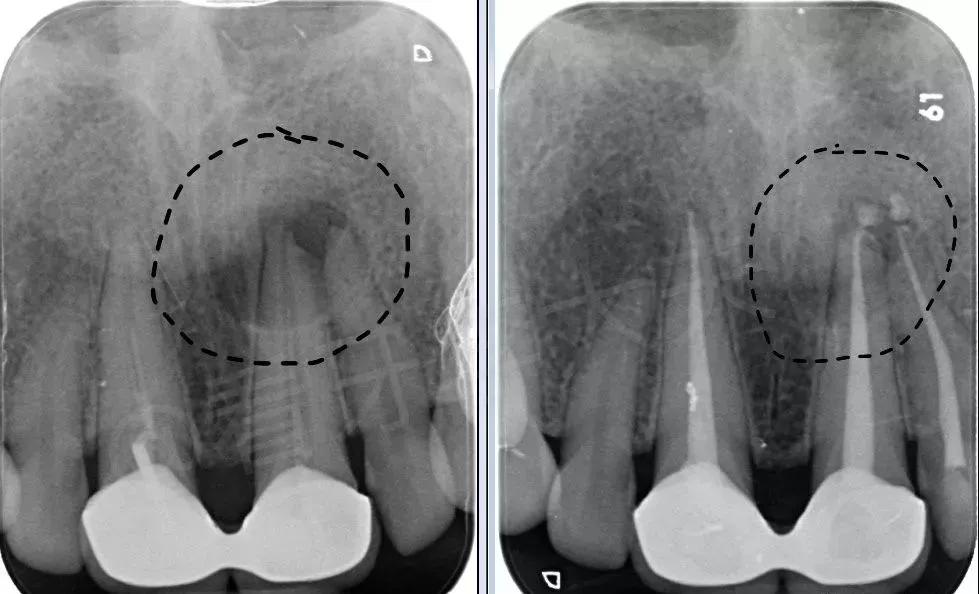

1.X光检查。X光片可看到龋坏的范围、根尖周围的病变,以及曾经做过的治疗情况。复杂的病例可能还需拍摄锥形束CT来帮助诊断。下图的根尖X光片可以看到曾经牙齿的根管填充不足(可在后文对比图中看出),以及牙齿根尖处的病变(黑色虚线圈出的圆形阴影)。

可看到根尖周围的病变,以及曾经做过的(不合格)的根管治疗

下图是一位患者治疗的前后对比。右图为治疗后2个月,可以看到阴影区域颜色明显变浅,证明感染愈合,牙槽骨正在形成。

治疗前(左)后(右)对比